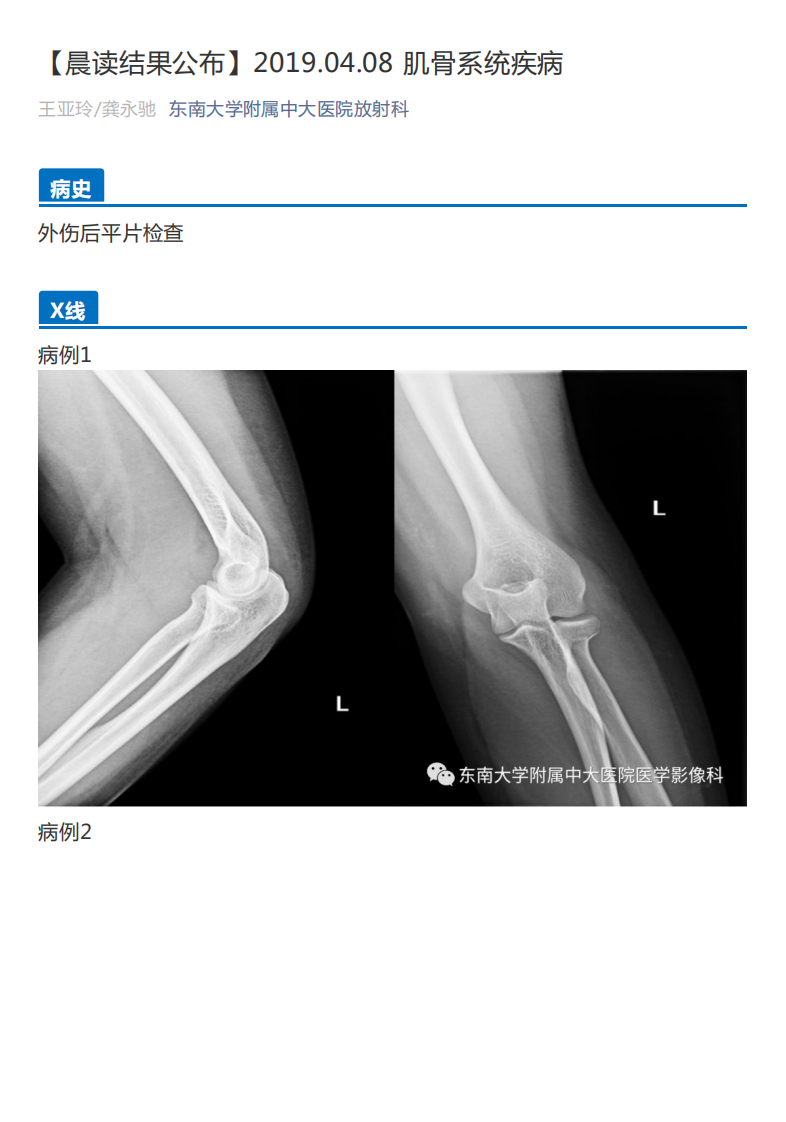

20190409_2【晨读结果公布】2019.04.08肌骨系统疾病.pdf